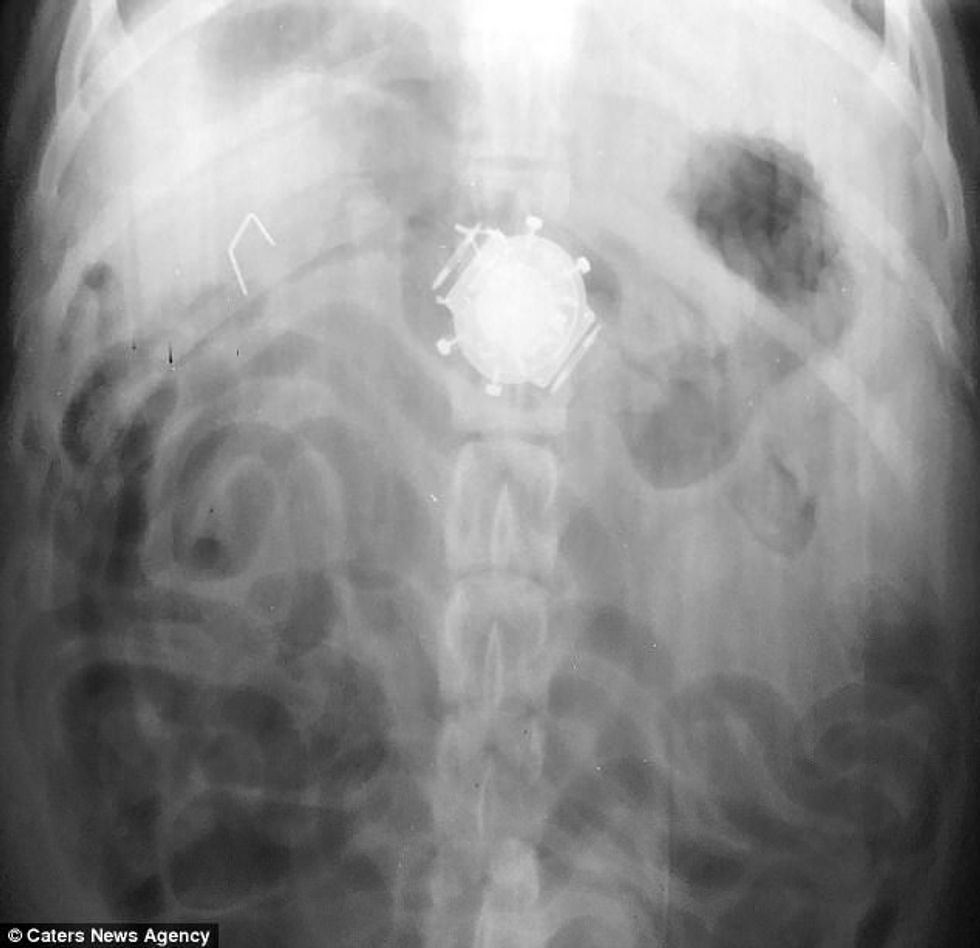

Skanimet kanë treguar për rastet më të pazakonta, prej lidhëseve të gomës, parave apo lugëve, që qentë i hëngrën duke menduar se janë ushqim. /Telegrafi/